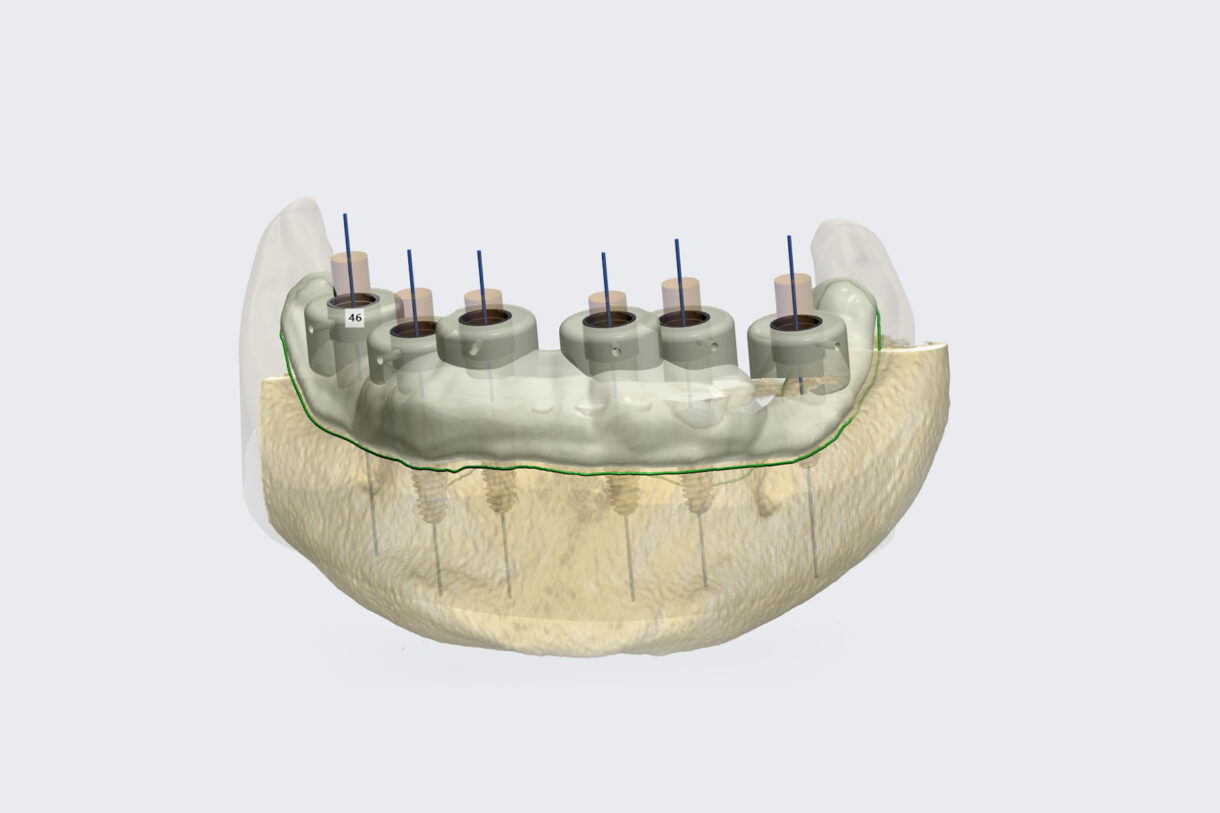

Before any implant procedure, planning is required. Today's technological possibilities are such that the whole process, from implantation to finished work, can be planned in advance. LiderDent uses photographs, intraoral scanning of teeth, three-dimensional X-ray CBCT images and software programs to plan the operation itself, as well as software for planning tooth making. The basic principle of planning is...